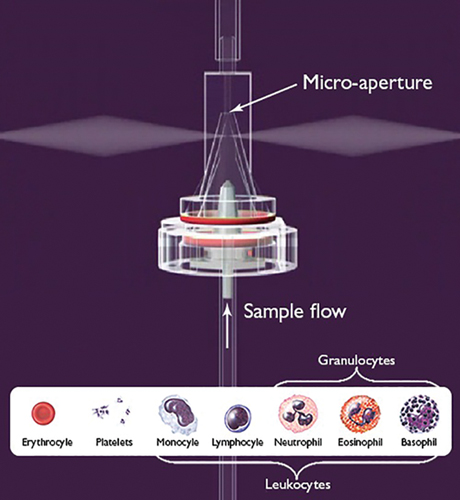

At the center of HORIBA Medical’s cutting-edge hematology analysis equipment is a well-known approach to blood analysis that uses a combination of optical measurement and electrical impedance to analyze a sample. The impedance measurement device utilizes a micro aperture-electrode system through which blood passes (see Figure 1). Electrical impedance is then used to count the number of cells and measure the size and distribution of erythrocytes (red blood cells), platelets, and leukocytes (white blood cells). After impedance measurement, a laser and optical detector are used to sort the different types of leukocytes.

Figure 1 — Diagram of the aperture-electrode system present in the ABX Pentra Series Analyzers

Isèbe uses COMSOL Multiphysics to improve the electrical impedance system in the Pentra Series (see Figure 2), one of HORIBA Medical’s most advanced hematology analyzers. The fully-automatic process begins with the placement of a blood sample in an analysis chamber, where it travels through a hydraulic channel and is then diluted with reagents. After dilution, the sample is sent into a counting and measurement chamber that consists of a micro-aperture flanked by a pair of electrodes (see Figure 3).

The electrodes generate a strong electrical field inside the counting chamber, and as the particles within the blood sample pass through the micro-aperture, the electrical impedance of the medium induces a change in voltage between the two electrodes. This voltage difference is then used to count the number of particles and determine the particle’s size, with a greater voltage difference corresponding to a larger molecule (see Figure 3).

Figure 3 — Principles of impedance measurement